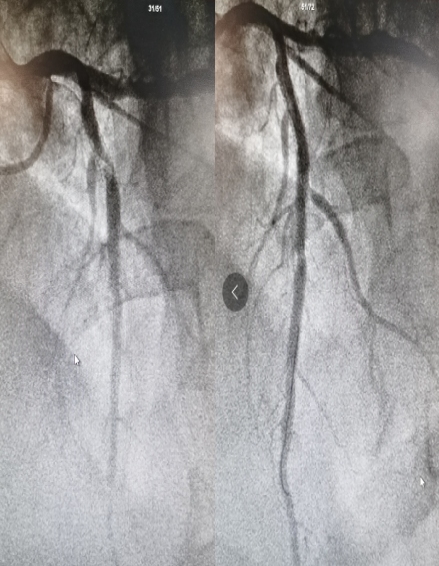

81岁男性患者,7年前因急性心肌梗死植入2枚支架,这次因“持续胸痛4小时”在当地县医院诊断为“急性前壁ST段抬高性心肌梗死”并行静脉溶栓治疗,溶栓同时联系120转入呼和浩特市第一医院。心血管内科高江峰主任接到通知立即组织人员启动导管室,患者转入后直接行冠脉造影,冠脉造影显示:患者前降支原支架内98%狭窄伴血栓。支架内再狭窄,为药物球囊扩张的绝对适应症。当日正赶上药物球囊降价的当口,该患者成为呼和浩特市第一医院首位享受集采优惠价药物球囊的患者,使用的药物球囊由原来的单个28000元降价到6297.70元。

药物球囊治疗前后对比图